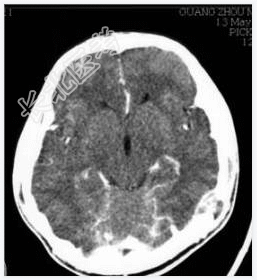

- [材料题] 病历摘要:男性,20岁。

主诉:发现头皮软组织肿物3个月。

现病史:三月前发现左枕部软组织轻微突起伴隐痛,到当地医院检查发现左枕部颅骨骨质缺损,未作具体治疗,现觉头皮肿物增大,时伴有气促、头痛。

专科检查:左颞枕部软组织略膨起,较软,各项病理反射(-)。

- 简答题1、诊断及诊断依据是什么?